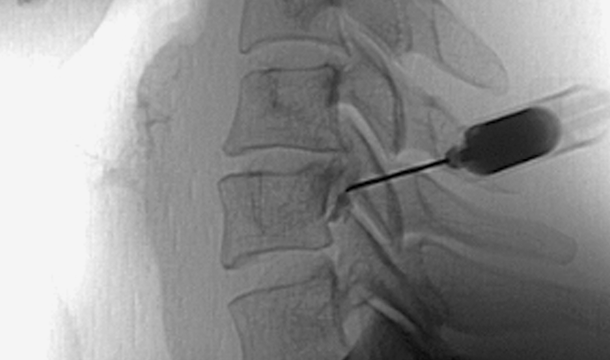

실시간 영상장치(C-arm)를 통해 통증의 원인 부위에 약물을 주입하여 통증을 차단하는 비수술적 치료법입니다.

실시간 영상장치(C-arm)로 정확한 치료 부위를 확인합니다.

통증 유발 신경에 치료 약물을 주입합니다.